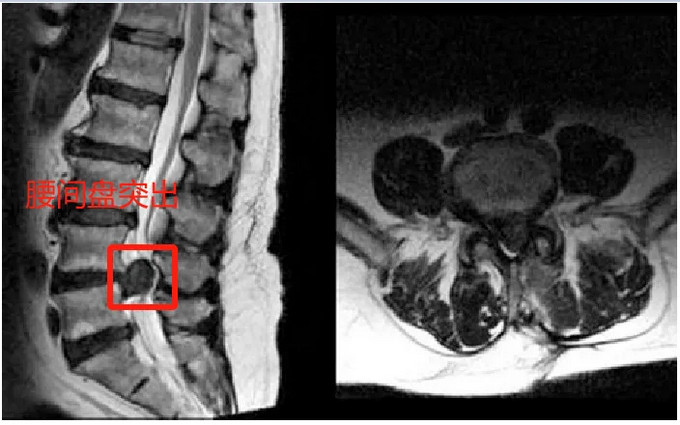

CT和MRI檢查是診斷腰椎間盤突出癥的主要方法,MRI作為腰椎間盤突出癥的首選檢查方法,能更準(zhǔn)確地提供關(guān)于椎間盤變性、硬膜囊受壓、脊髓變形、神經(jīng)根受壓、椎間盤突出等多種影像學(xué)特征的詳細信息。其準(zhǔn)確率高于CT,但CT的價格低于MRI,可作為初診患者的檢查方法。同時由于腰椎間盤突出癥髓核突出壓迫神經(jīng)易出現(xiàn)表現(xiàn)為神經(jīng)傳導(dǎo)速度減弱的肌電圖表現(xiàn)。腰椎間盤突出癥患者檢驗一般炎癥指標(biāo)血沉、CRP正常,HLA-B27陰性。

圖片來源于百度

而強直性脊柱炎的腰痛主要是由于炎癥介導(dǎo),隨著病情進展,骶髂關(guān)節(jié)CT主要表現(xiàn)為骶髂關(guān)節(jié)面的粗糙不平、骨質(zhì)硬化、關(guān)節(jié)間隙狹窄或消失,嚴(yán)重者可出現(xiàn)脊柱的竹節(jié)狀改變等。AS活動期血沉、C反應(yīng)蛋白大多升高,HLA-B27陽性。